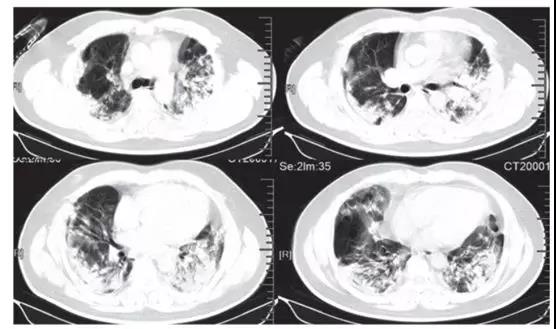

ICU患者入院時胸部CT圖像的典型發現,是雙側多發小葉和亞段實變(見下圖)。